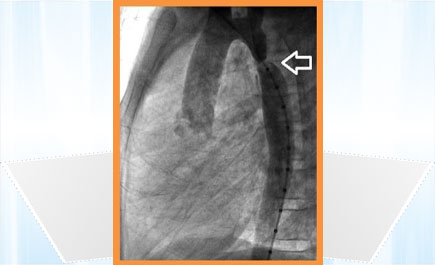

توسيع الشريان «الأورطي» لطفل

تمكن فريق طبي في مركز الأمير سلطان لطب وجراحة القلب في القصيم من إنهاء معاناة طفل في العاشرة من العمر كان يعاني من تضيق شديد في الشريان الأبهر «الأورطي»، وذلك عبر إجراء عملية توسيع للشريان المتضيّق عبر القسطرة العلاجية التداخلية، ومن ثم زراعة دعامة بمقاس مناسب أعادت الشريان «الأورطي» إلى حالته الطبيعية، مما ساهم في تجنيب الطفل جراحة القلب المفتوح، وقد خرج الطفل من المركز في نفس اليوم وهو بحال صحية جيدة، وتعد هذه العملية هي الأولى التي تجري في منطقة القصيم.